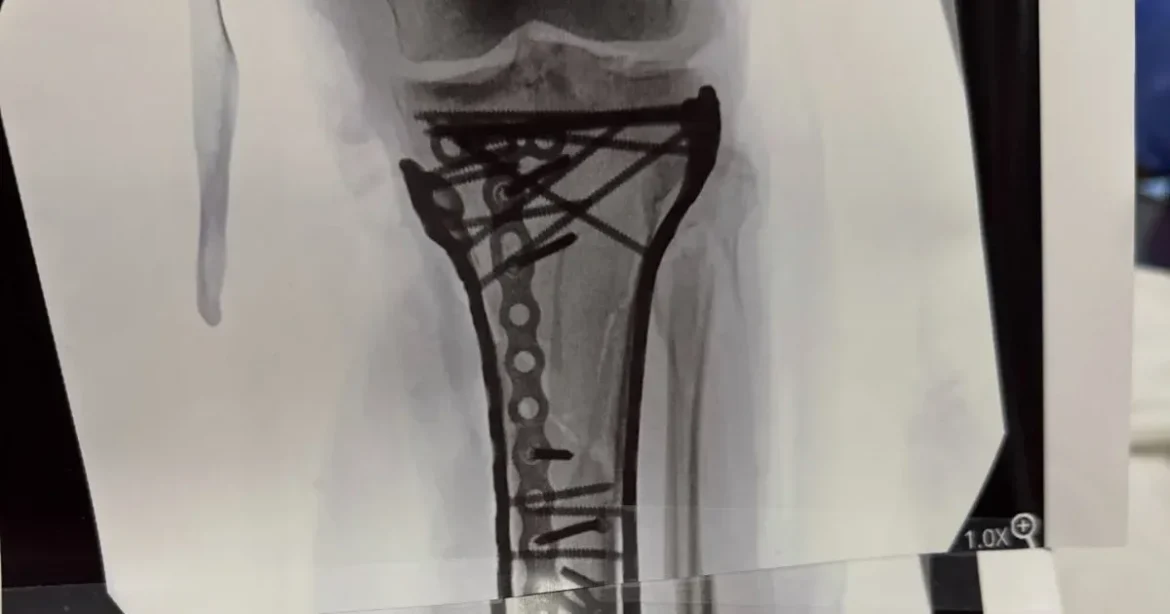

A sérülése után Vonn Olaszországban négy műtéten esett át, majd az ötödik operációt az Egyesült Államokban, Vailben végezték el. Az utolsó beavatkozás több mint hat órán át tartott, amely során a híres orvos, Tom Hackett ismét részt vett a rehabilitációs folyamatban. Vonn Instagramjára posztolt róla, hogy mennyi fémcsavar, lemez és szegecs került a lábába, és a röntgenképen is dokumentálta a fejlődést.